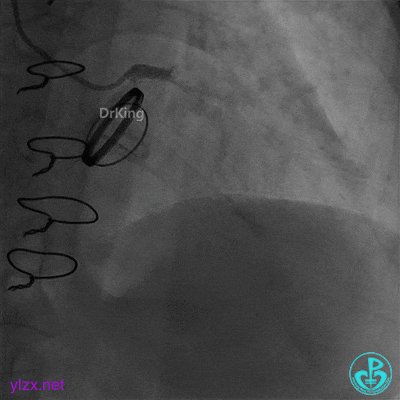

05 急诊冠脉造影

前降支血流3级,前降支近段、对角支开口大量血栓,回旋支开口闭塞。